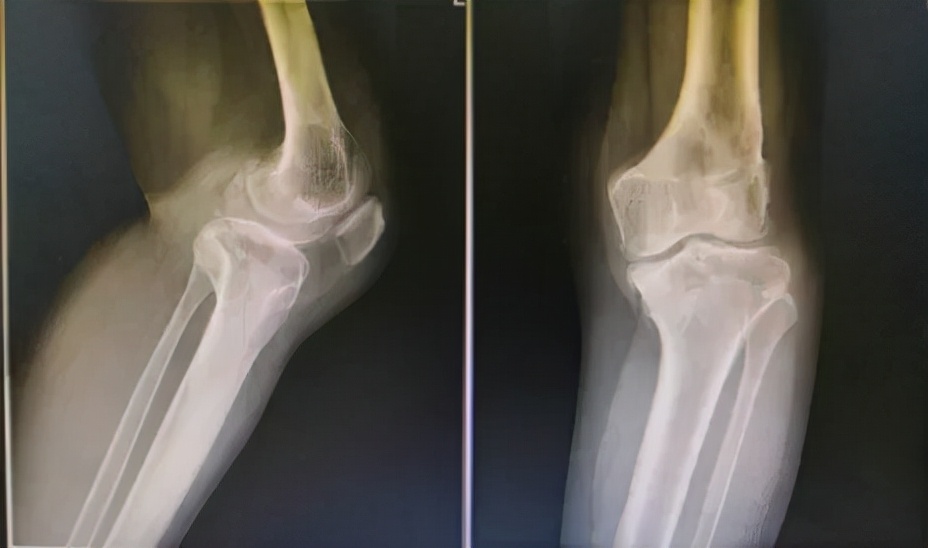

54岁的赵女士在10年前出现左膝关节疼痛,近半年来症状加重。有持续中到重度的疼痛,行走活动时加剧,同时伴有膝关节屈曲受限。目前赵女士的膝关节重度疼痛,药物保守治疗无效,为求进一步诊治,她来到上海市第六人民医院骨科,门诊以左膝关节炎收入病房。

入院后刘万军主任对赵女士进行了详细的检查发现,赵女士的左膝关节存在严重的内翻畸形,关节间隙明显缩小。不仅股骨侧存在畸形,且胫骨侧也存在畸形。当股骨和胫骨均存在畸形时,试图仅通过胫骨侧截骨或股骨侧截骨来矫正这类畸形可能会导致术后关节线发生非生理性倾斜,使得关节表面软骨遭受的剪切力增加。长期的剪切应力会使得软骨超过其承载负荷的极限,造成软骨面的损伤,加快骨关节炎的发生和进展。此外,关节线倾斜还可能引起膝关节周围韧带的松弛,从而在负重时容易产生半脱位。因此,刘万军主任团队准备对赵女士的左膝关节同时进行股骨远端截骨术+胫骨高位截骨术(DFO+HTO),以此矫正左膝严重内翻畸形,更好地恢复关节力线和膝关节的正常解剖角度。

术前